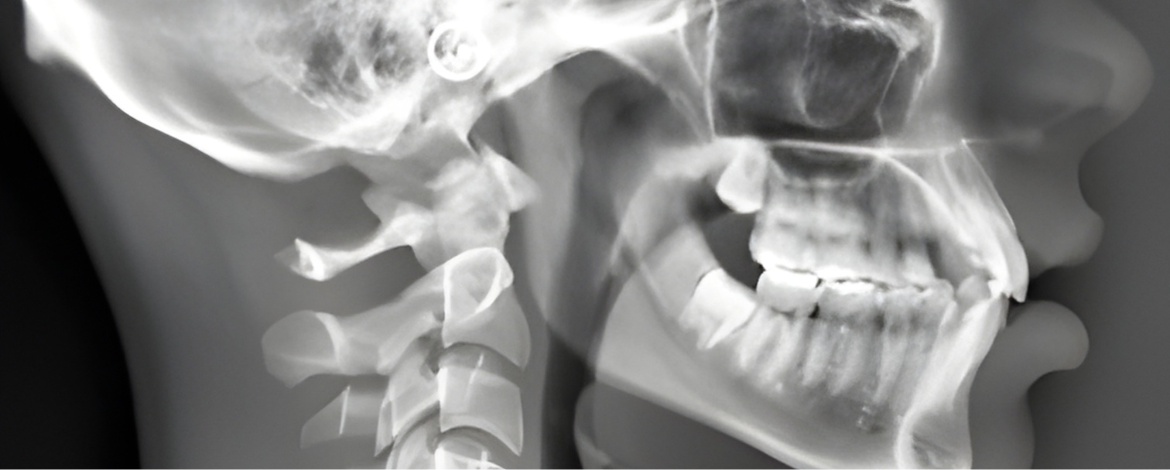

A Telerradiografia Odontológica é um exame de imagem essencial no planejamento e acompanhamento de tratamentos ortodônticos. Por meio de uma radiografia lateral do crânio, o exame permite uma análise detalhada das estruturas ósseas da face, da posição dos dentes e do crescimento facial.

Esse exame é fundamental para que o ortodontista avalie com precisão o desenvolvimento ósseo, o alinhamento facial e a relação entre maxila, mandíbula e dentes, garantindo decisões clínicas mais seguras e resultados mais previsíveis.